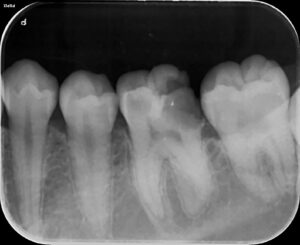

さらに、特に進行が目立つ部分を拡大して撮影したものがこちらです。

いかがでしょうか。 歯の内部に、黒く大きな空洞(透過像)が広がっているのがお分かりいただけるでしょうか? 2年前には影も形もなかった虫歯が、わずか2年で神経の近くまで破壊を進めてしまっているのです。